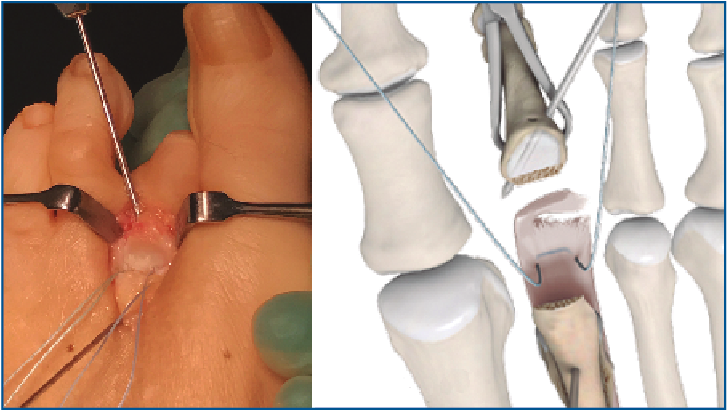

6. Retiramos el distractor y la agK de la falange, y realizamos 2 pequeños túneles de dorsal a plantar en la base de F1 con una broca o agK de 1,2 mm (Figura 10). Estos pueden disponerse cruzados o en paralelo. Aunque la disposición paralela pudiera teóricamente debilitar la base de F1 al ser prácticamente subcondrales, realizarlos cruzados tiene la desventaja de poder interferirse en el pase de las suturas. A través de estos túneles recuperamos las suturas preparadas en el extremo distal de la placa, de plantar a dorsal (Figura 11 y Vídeo).

7. Fijamos la osteotomía de Weil con el acortamiento metatarsal deseado y previamente establecido (se recomienda un acortamiento mínimo de 2-3 mm) (Figura 12). Con la articulación MTF perfectamente reducida y el dedo en 30° de flexión plantar, tensamos las suturas recuperadas en el dorso de F1, hasta llevar firmemente la placa plantar a su base, y anudamos (Figura 13).

Figura 10. Doble tunelización en base de F1.

Figura 11. Recuperación de las suturas de plantar a dorsal, a través de los túneles de F1.

Figura 12. Fijación de la osteotomía de Weil con el acortamiento deseado (mínimo 2-3 mm).

Figura 13. Tensado y anudado individual de las suturas en el dorso de F1, confirmando la reducción estable de la articulación metatarsofalángica.